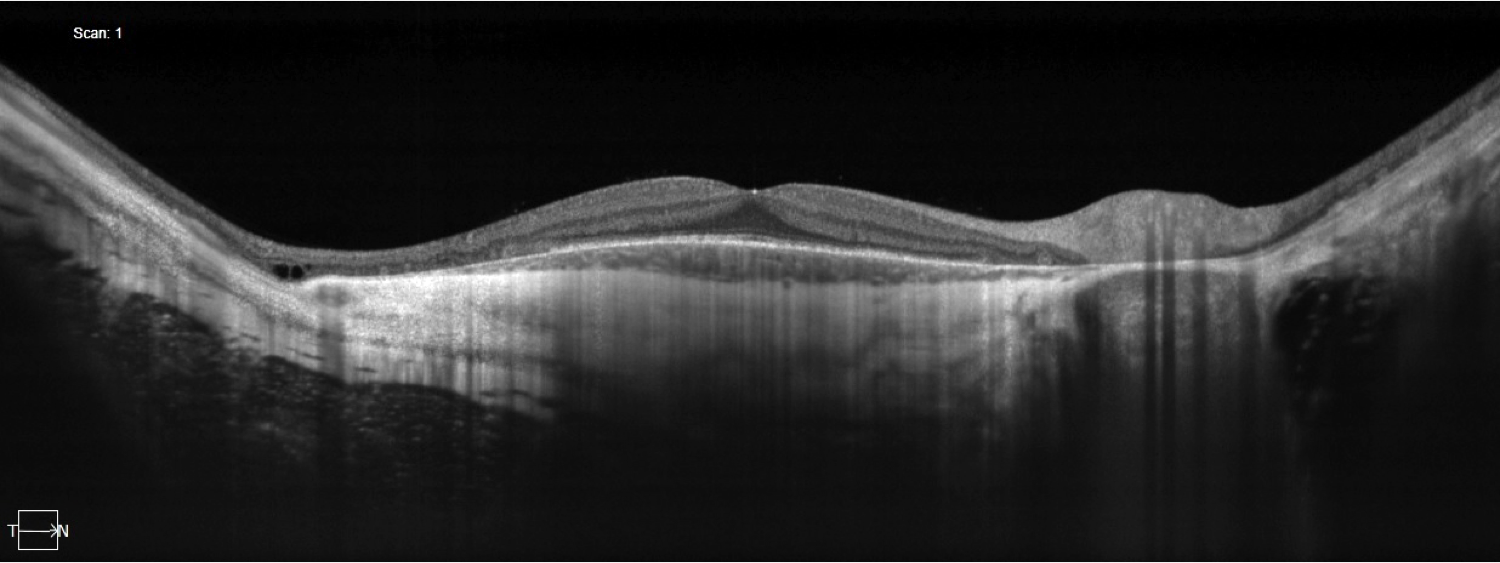

Sixteen millimeter Swept source OCT line scan of the right eye.